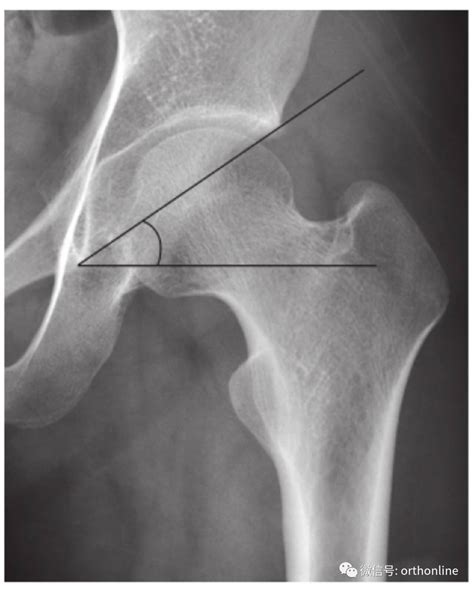

双侧髋臼发育不良【双侧髋臼发育不良】